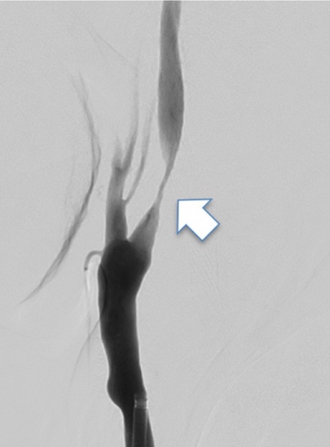

動脈の内部にプラークという脂の塊が貯まることで血管が細くなる病気です。脳梗塞の原因となります。ある程度のものであれば内服薬のみで脳梗塞予防が可能になってきていますが、重度のものでは外科的な治療が必要になります。

血管内治療では、狭窄部位にステントを留置することで狭窄した血管を広げることが可能です(下図)。

治療前

治療後